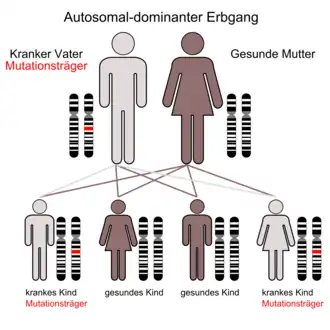

Die Neurofibromatose Typ 1 (kurz: NF1), auch Von-Recklinghausen-Krankheit, Morbus Recklinghausen, kurz auch Neurofibromatose Recklinghausen (benannt nach ihrem Entdecker Friedrich Daniel von Recklinghausen) oder periphere Neurofibromatose, ist eine autosomal-dominant und monogen vererbte Multiorganerkrankung, bei der es zu multiplen Neurofibromen peripherer Nerven und zu Hautmissbildungen kommt.

Man schätzt etwa 30 bis 40 Erkrankte auf 100.000 Einwohner, was einer Erwartung von einem betroffenen Kind pro 2500 bis 3300 Geburten entspricht. In der Hälfte der Fälle geht man davon aus, dass eine Neumutation zu den Veränderungen im Erbgut führt. Alle bisherigen Beobachtungen bestätigen den autosomal dominanten Erbgang, was bedeutet, dass ein betroffener Elternteil mit einer Wahrscheinlichkeit von 50 Prozent die Erkrankung an seine Kinder weitergibt. Man findet keine unterschiedlichen Häufigkeiten in verschiedenen Regionen der Erde oder unter Angehörigen anderer ethnischer Gruppen. Allerdings erkranken Männer etwas häufiger als Frauen. Die hohe Rate der Neumutation wird mit dem Umstand erklärt, dass das NF-1-Gen sehr groß ist und somit viel Angriffsfläche für genetische Veränderungen bietet.[1]